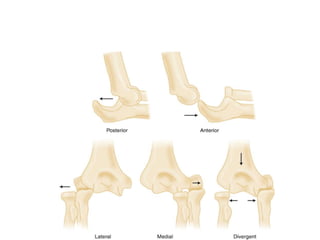

Elbow dislocation

• Posterolateral is the most common type of

dislocation (80%)